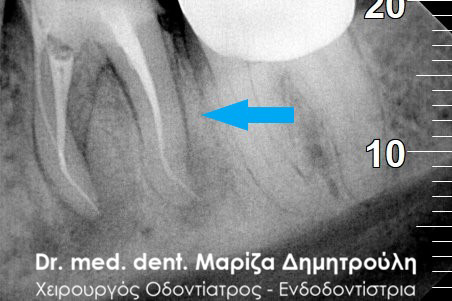

Περιστατικό – Στεφάνη / θήκη δοντιού

Ο ασθενής επισκέφτηκε το ιατρείο καθώς έσπασε ο άνω αριστερός προγόμφιος. Το συγκεκριμένο δόντι είχε μία παλία απονεύρωση δοντιού, η οποία περιοδικά έδινε συμπτώματα πόνου στον ασθενή. Μετά την κλινική και ακτινογραφική εξέταση του δοντιού αποφασίστηκε η επανάληψη της απονεύρωσης δοντιού και η προστασία του δοντιού με θήκη.

Ακτινογραφική εικόνα του δοντιού πριν την επανάληψη της απονεύρωσης

Ακτινογραφική εικόνα του δοντιού μετά την επανάληψη της απονεύρωσης